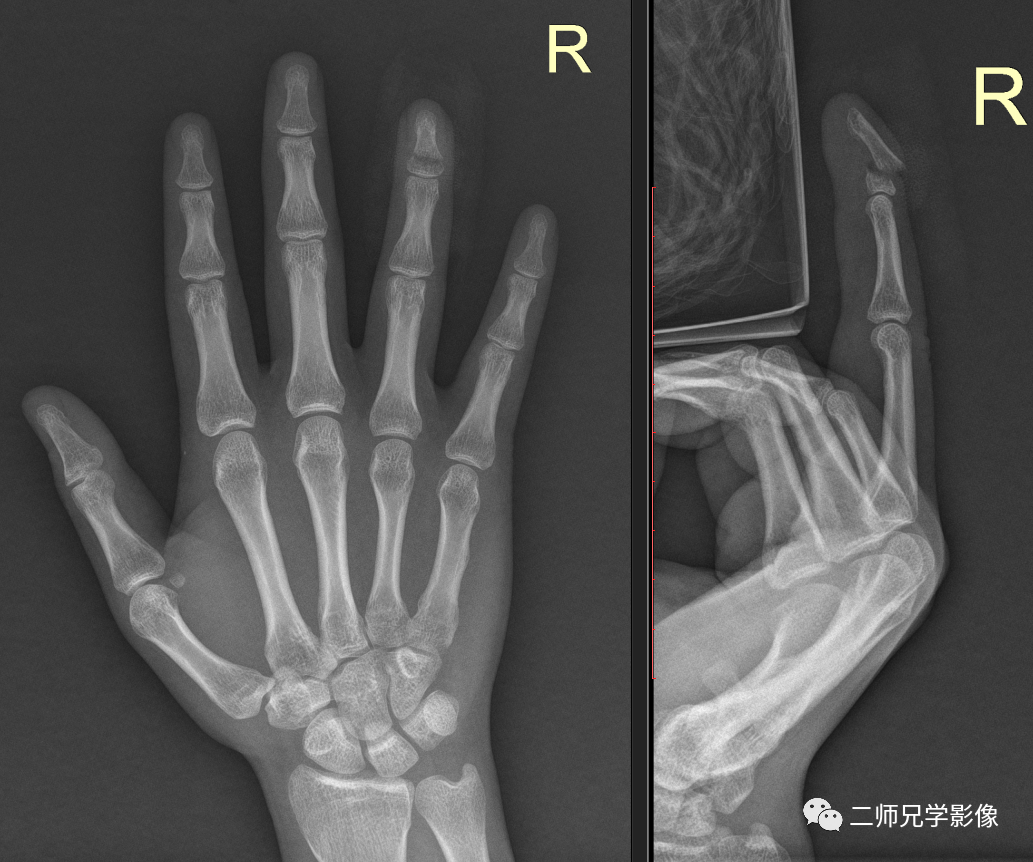

病例四:病人右手指外伤,申请单:右手指正侧位

怎么取放射片放射拍片中的“几何学”,临床医生和技师都掌握了吗?_https://www.jmylbn.com_新闻资讯_第13张

右手第4指远节骨折,远端后移